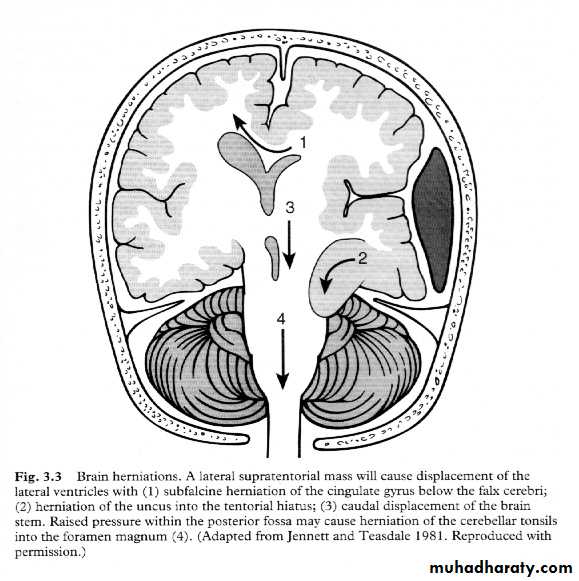

7. Cerebral Herniation

a. Subfalcine Herniation

b. Uncal Herniation

c. Tentorial Herniation

d. Tonsillar Herniation